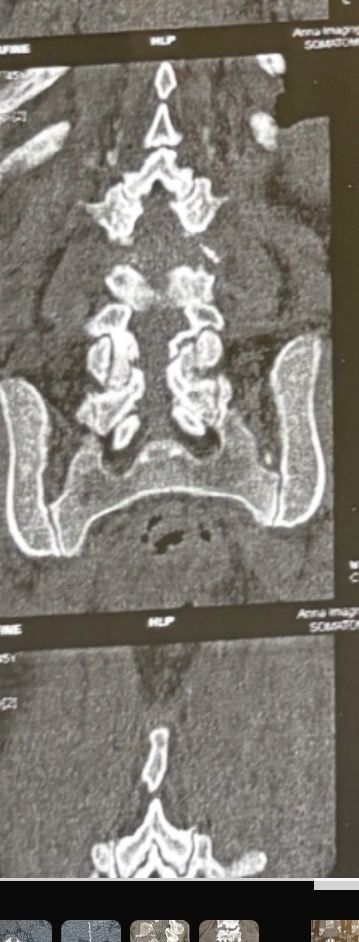

Few weeks ago I posted a case with an old TB spondylitis and listhesis with old fractures and severe canal stenosis (in her lower lumbar). A neurosurgeon who works with us at my clinic saw her in the second session

I attached her CT scan. Her PPD which was positive 2 months ago now it’s less than 3 mm. Since this patient has just low back pain and no radicular pain and can walk easily our neurosurgeon suggested no surgery and we emphasized that she has to complete her medication and be under her infectious diseases specialist

And if other signs and symptoms develops have to see surgeon again

42 years old female presented to my clinic yesterday on May15/2025 with chronic Low back for 2 yrs. She is from afghanestan and arrived to tehran 3 month ago. Visited pain specialist 3 months ago who just did PPD test and gave her Anti TB medication. In examination just had severe focal khyphosis from L3 to L5 without any tenderness. Her mri was done 2 months ago. Report is in Farsi and mentions of paraspinal puss/ fluid collection esp in psoas muscles, with extension of fluid collection to R pelvic region. Had 2 site of severe canal stenosis due to previous fractures of L3,4,5 and movement of fractured bones to the canal with complete distractions of those levels discs with fusion of L3 to L5

I ordered C T scan of lumbar and pelvic MRI / chest x r and reffered her to neurosurgon and infectious disease specialist to get full assessment and possible hospitalized for biopsy and surgery

As you know doctors of chiropractic would never. give treatment to patients with spinal Discitis/ osteomyelitis/ metastasis/ fracture( absolute chiropractic contraindications for treatment)